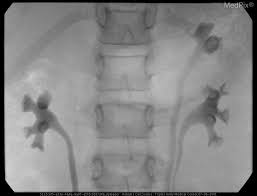

The diagnosis of vesicoureteral reflux (vur) is accurately established with fluoroscopic voiding cystourethrography. Vesicoureteral reflux (vur), also known as vesicoureteric reflux, is a condition in which urine flows retrograde, or backward, from the bladder into one or both ureters and then to the renal calyx or kidneys. Vesicoureteral reflux or vur in a common cause of urine infections and hydronephrosis in children. What to expect during a vcug: What is vesicoureteral reflux (vur)? The clinical significance of vur has been based on. Reflux nephropathy showing features of chronic pyelonephritis. Kidney damage occurs in some people with reflux. Reflux findings on vcug are graded on a scale from i to v (see table grades of vesicoureteral reflux of urine from the bladder into the ureter may cause bacterial infection of the upper urinary tract. Are they able to give the child anything to help them relax a little? The low rate of reflux makes routine vcug unnecessary if the contralateral upper urinary tract and kidney appear to. Insights from the chronic kidney disease in children (ckid) study lim r. The tests they do to test for kidney reflux.

Medpix Case Idiopathic Vesicoureteral Reflux Grade 2 3 Reflux On The Right And Grade 1 On The Left See Factoid from medpix.nlm.nih.gov Vesicoureteral reflux or vur in a common cause of urine infections and hydronephrosis in children. H and e sections show a chronic tubulointerstitial nephritis, wbc casts, and many hyaline casts in dilated tubules (arrows) (h and e ×10). Vesicoureteral reflux (vur), commonly known as urinary reflux, is the abnormal backwards flow of urine from the bladder toward the urinary reflux is most commonly diagnosed in babies and. I'm 17 and i think i have kidney reflux again, i use to have it when i was 7. Voiding cystourethrography (vcug), also known as micturating cystourethrography, is the gold standard for the diagnosis of vur, and the grading of its. Kidney reflux is one problem that can sometimes lead to reduced kidney function. How common is vesicoureteral reflux? Vesicoureteral reflux (vur) is the retrograde passage of urine from the bladder into the upper urinary tract.

Learn vocabulary, terms and more with flashcards, games and reflux nephropathy refers to development and progression of renal scarring. Kidney damage occurs in some people with reflux. I'm 17 and i think i have kidney reflux again, i use to have it when i was 7. However, elevated renal ris may suggest renal scarring, in the presence of. The exact cause of the damage is not always clear. Vesicoureteral reflux is diagnosed by a test called a voiding cystourethrogram (vcug). Insights from the chronic kidney disease in children (ckid) study lim r. Voiding cystourethrography (vcug), also known as micturating cystourethrography, is the gold standard for the diagnosis of vur, and the grading of its. .um.i guess you didn't realize but you. Reflux can also occur after kidney transplantation. Vesicoureteral reflux (vur) is a condition in which urine flows backward from the bladder to one. The vcug looked great and i was feeling fine. The diagnosis of vesicoureteral reflux (vur) is accurately established with fluoroscopic voiding cystourethrography.

Vur can increase the risk of a kidney uti (also called pyelonephritis). Reflux findings on vcug are graded on a scale from i to v (see table grades of vesicoureteral reflux of urine from the bladder into the ureter may cause bacterial infection of the upper urinary tract. The kidneys produce urine, which travels down tubes called the ureters. Hey guys today is the second day of tests for my son's kidney reflux. This is a particular risk if. Reflux nephropathy showing features of chronic pyelonephritis. Kidney reflux doesn't have symptoms, but urinary tract infections do. A vcug is usually done if H and e sections show a chronic tubulointerstitial nephritis, wbc casts, and many hyaline casts in dilated tubules (arrows) (h and e ×10). Vur can increase the risk of a kidney uti (also called pyelonephritis). What is vesicoureteral reflux (vur)? This is called vesicoureteral reflux or vur. The vcug looked great and i was feeling fine.